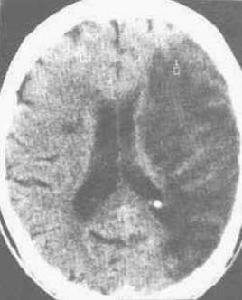

該病的診斷主要為CT或MRI檢查。